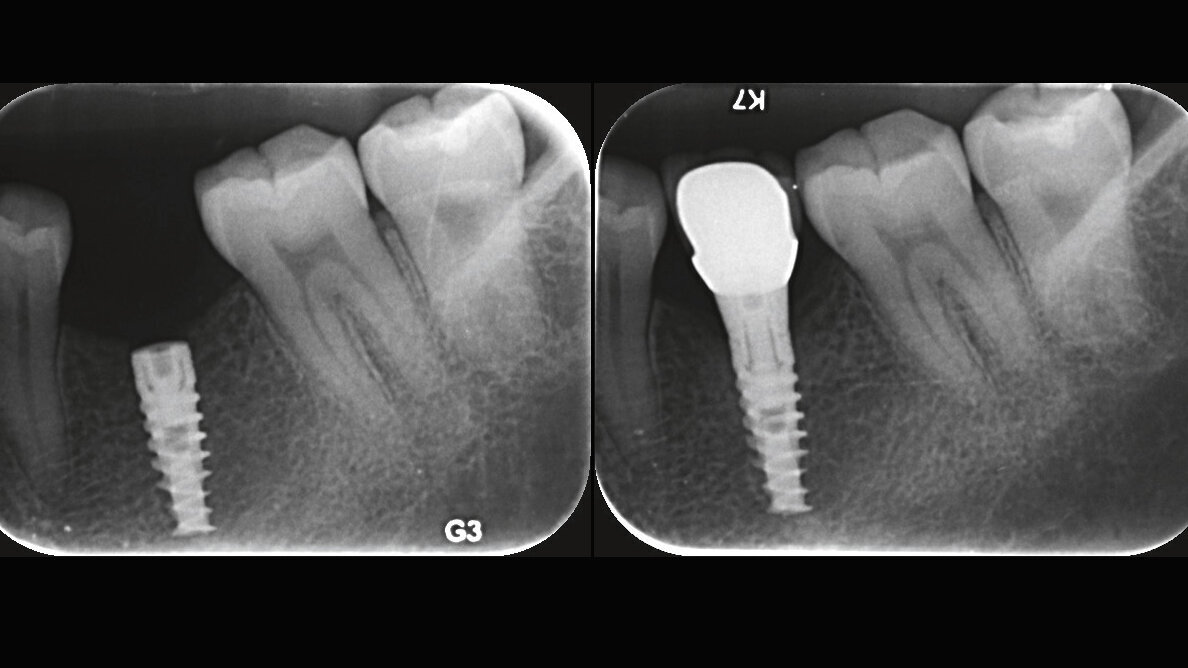

Left: SPI implant immediately after implantation surgery. Right: SPI implant 2 years after implantation surgery. (Image: Prof. Ofer Moses)

Materials and methods: This multicenter prospective clinical study was performed in partially edentulous subjects. The patients treated in the study received 1–4 SPI implants (Alpha-Bio Tec, Petah Tikva, Israel), which were loaded four months after implantation. Measurements of torque and RFA were recorded immediately after implant insertion. New RFA measurements were taken at the time of implant exposure surgery, prior to connection of the healing abutments. Baseline measurements of bone level were taken both directly and radiographically immediately after insertion and were compared with measurements taken during the two-year follow-up period.

Results: Of 88 treated subjects, 83 completed the two-year follow-up. Of 137 implants, five were lost. The survival rate after two years of follow-up was 96.5 percent and the mean marginal bone loss was 0.531 mm. The mean measurement for RFA at the time of implantation was 74.92 and this increased to 76.26 prior to insertion of the prostheses.

Conclusion: Within the limits of the study, implants inserted with low torque (< 35 N cm), displayed high survival rates with high RFA scores and minimal bone loss at the two-year mark after implantation.